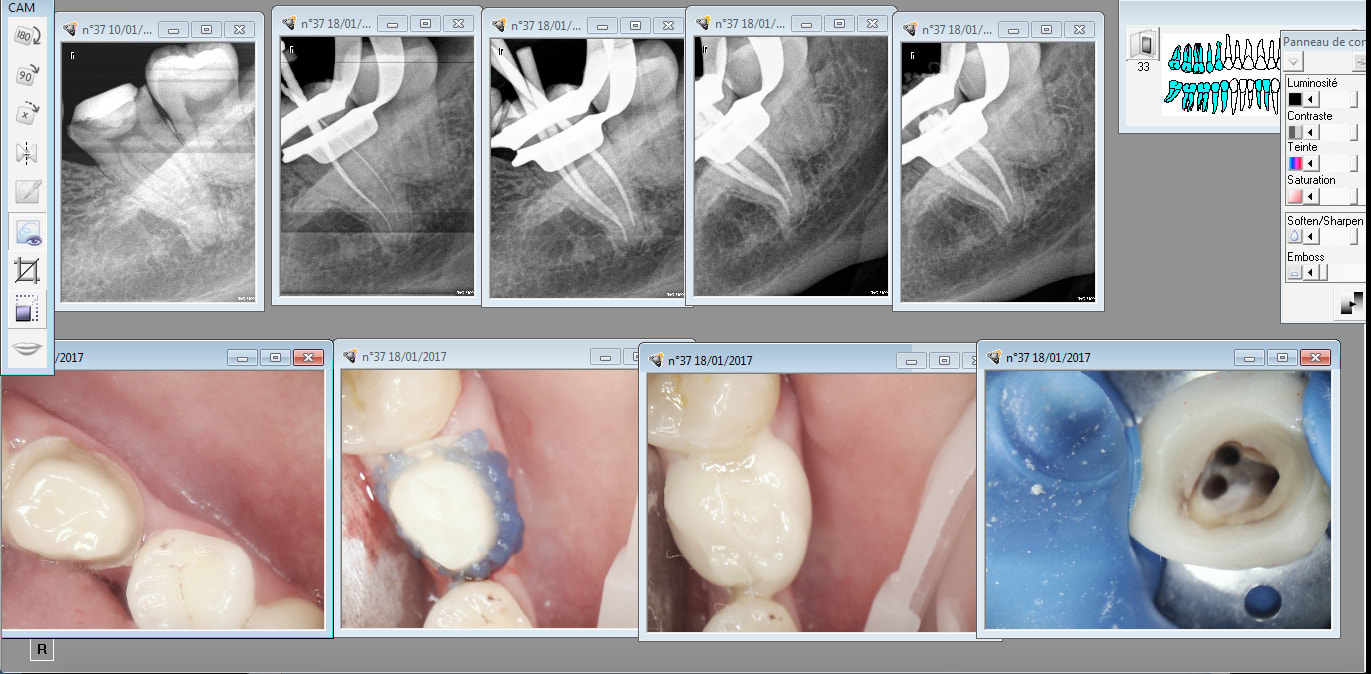

Tu vois on arrive pas à l'apex tout le temps. Mais ca reste exceptionnel. -)

A mon avis les 3 sont en Y.

Genre d'image à joindre à la feuille de sécu. Combien ca vaut ? -)

Il y a mon capteur qui commence à merder par intermitence. Faut dire qu'il en a copieusement reçu des X rays. Je ne te racontes pas à quel point il a été amorti. -)